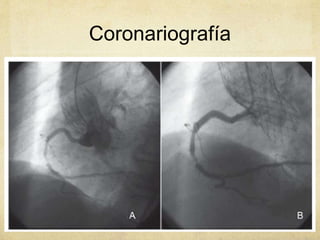

Coronariografí

a diagnóstica

Coronariografía